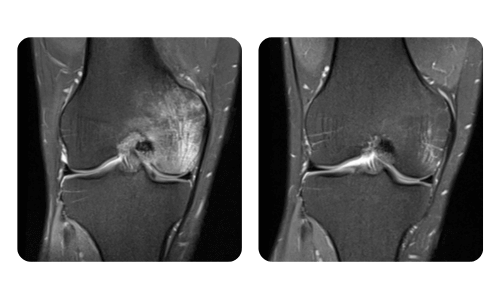

I progressi dei nostri pazienti, misurati prima e dopo la terapia iperbarica, riflettono l'efficacia e l'impatto positivo del trattamento. Scopri i risultati documentati della terapia iperbarica presso la clinica Hyperbarium Oradea, basati su valutazioni cliniche e dati oggettivi che evidenziano miglioramenti significativi in diverse condizioni.